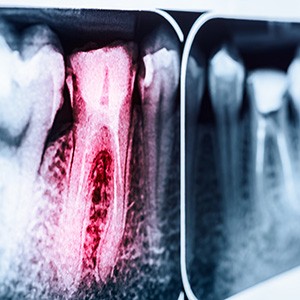

Root canal treatment is needed when the nerve of a tooth is affected by decay or infection. In order to save the tooth, the pulp (the living tissue inside the tooth), nerves, bacteria, and any decay are removed, and the resulting space is filled with special, medicated, dental materials, which restore the tooth to its full function. Having a root canal done on a tooth is the treatment of choice to save a tooth that otherwise would die and have to be removed. Many patients believe that removing a tooth that has problems is the solution, but what is not realized is that extracting (pulling) a tooth will ultimately be more costly and cause significant problems for adjacent teeth. At our dental office, root canal treatment in Cambridge is highly successful and the results usually last a lifetime, although on occasion, a tooth will have to be retreated due to new infections.

A root canal procedure requires one or more appointments and can be performed by a dentist or endodontist (a root canal specialist). While the tooth is numb, a rubber dam (a sheet of rubber) will be placed around the tooth to keep it dry and free of saliva. An access opening is made on top of the tooth and a series of root canal files are placed into the opening, one at a time, removing the pulp, nerve tissue, and bacteria.

If tooth decay is present, it will also be removed with special dental instruments. Once the tooth is thoroughly cleaned, it will be sealed with either a permanent filling or, if additional appointments are needed, a temporary filling will be placed. At the next appointment, usually a week later, the roots and the inside cavity of the tooth will be filled and sealed with special dental materials. A filling will be placed to cover the opening on top of the tooth. In addition, all teeth that have root canal treatment should have a dental crown (cap) placed. This will protect the tooth and prevent it from breaking and restore it to its full function. After treatment, your tooth may still be sensitive, but this will subside as the inflammation diminishes and the tooth has healed. You will be given care instructions after each appointment. To aid in the life of your root canal results, patients should practice good oral hygiene and have regular dental visits.